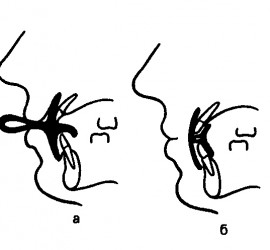

Характеризуя состояние слизистой оболочки протезного поля, Суппли выделяет четыре класса: Здоровая слизистая оболочка полости рта (умеренно податливая, умеренно подвижная, бледно–розового цвета). Атрофичная слизистая оболочка полости рта (малоподатливая, бледно–розового цвета, слабо увлажнена, с повышенной болевой чувствительностью); Слизистая оболочка с избыточной податливостью, чрезмерно увлажнена; Чрезмерно подвижная слизистая оболочка, расположена в области вершины […]